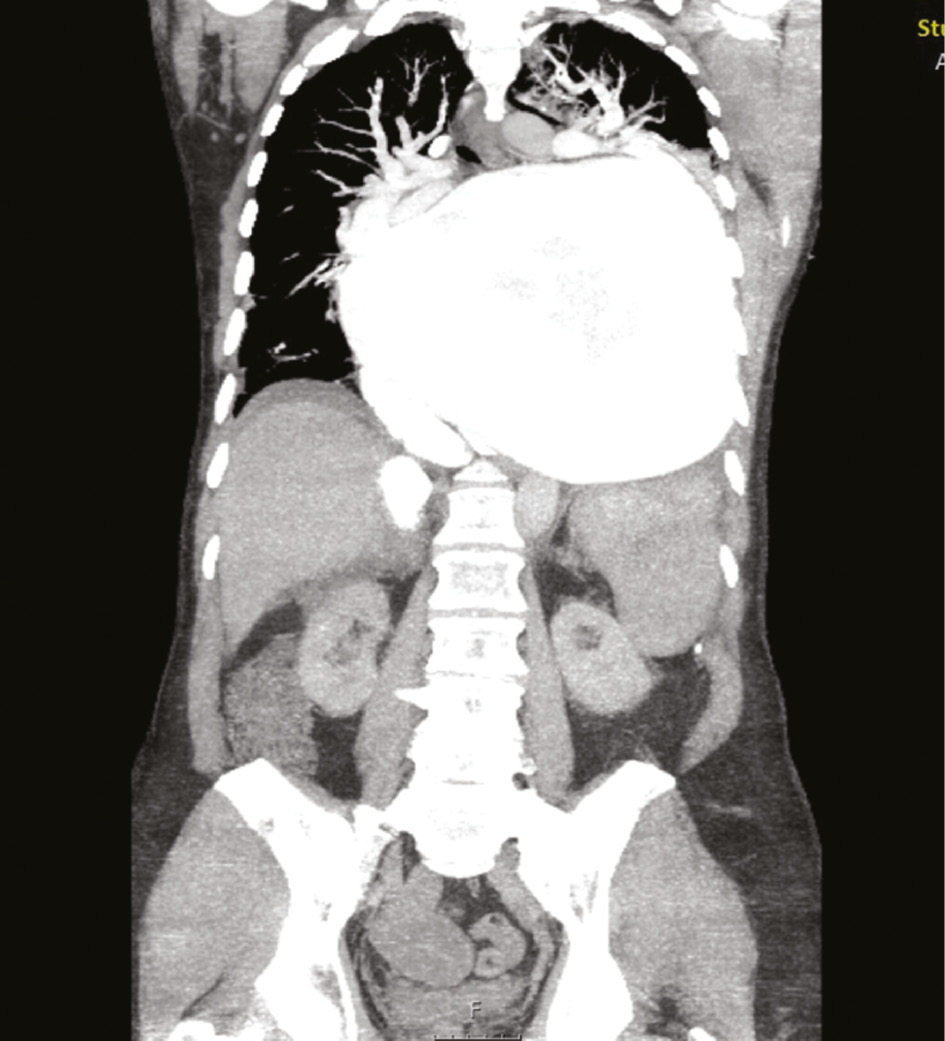

A 57-year-old male with acute heart failure was admitted to a community hospital after return of spontaneous circulation (ROSC) following cardiac arrest and approximately 65 min of out-of-hospital CPR. Although his cardiac rhythm at the time of ROSC was not documented, he was in atrial fibrillation upon arrival at the community hospital. It turned out that he had undergone redo mitral valve replacement with a mechanical valve and tricuspid valve repair 5 years preceding the event. Nearly two decades earlier, he had undergone mitral valve replacement for mitral regurgitation in the setting of cardiomegaly. Echocardiography (ECG) and computed tomography (CT) showed a grotesque case of GLA (Figures 1 and 2 ) that had gone undiagnosed because the patient had not presented for follow-up examinations after the most recent surgical procedure (i.e. for 5 years). ECG findings included sludge in GLA and a left ventricular ejection fraction of 10%. Fluoroscopy showed a normal motion of mitral valve leaflets.

Frontal section of GLA on initial CT.